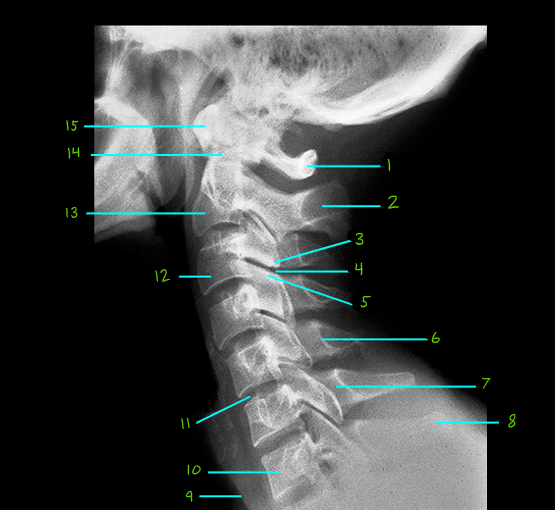

Cervical Spine Lateral View Flashcards

What is #1

Posterior Arch of the Atlas

What is #2

Spine of the Axis

What is #3

Inferior Articular Process

What is #4

Facet Joint

What is #5

Superior Articular Process

What is #6

Posterior Wall of the Vertebral Canal

What is #7

Lamina

What is #8

Spine of C7

What is #9

Soft Tissue Contour

What is #10

Body of C7

What is #11

Intervertebral Disc

What is #12

Body of C3

What is #13

Body of the Axis (C2)

What is #14

Odontoid Process (Dens)

What is #15

Anterior Arch of the Atlas (C1)